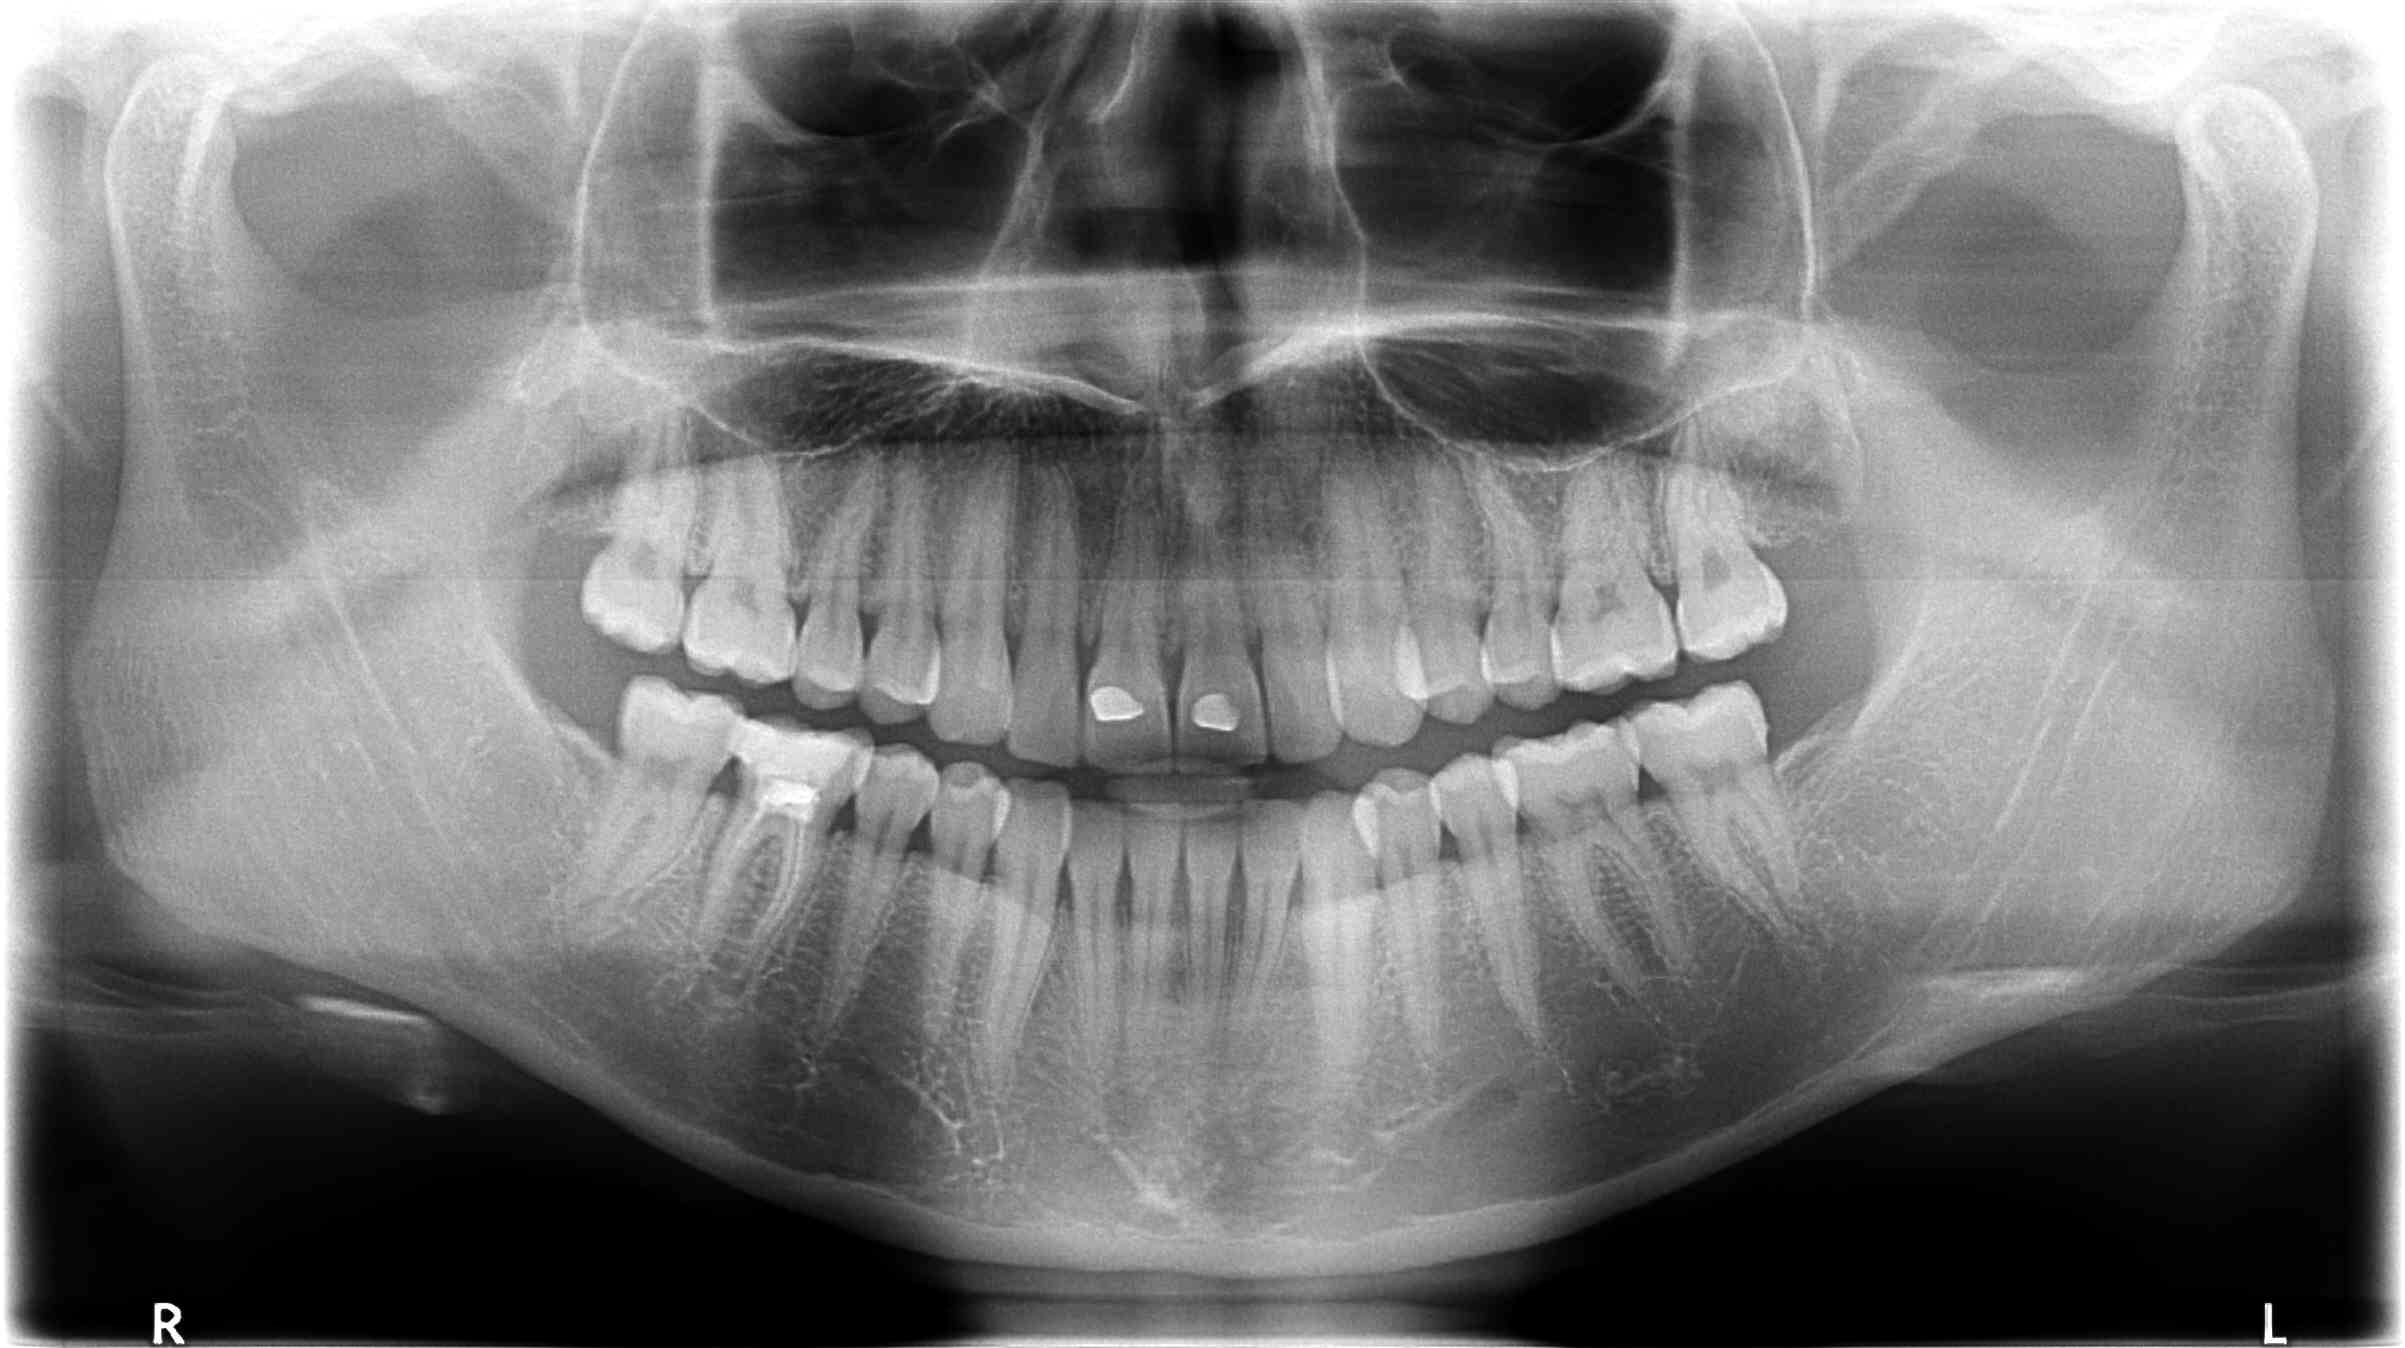

Implant dentium Superline 4x10 posé en 46 debut 2018 sur patiente bruxomane avec gouttiere.

Elle bruxe mais pas comme une folle non plus, sur la pano, les dents ne sont pas rasées non plus.

il semble que l os ne soit plus présent autour de l implant sur le col , y a t il un lien de cause a effet?